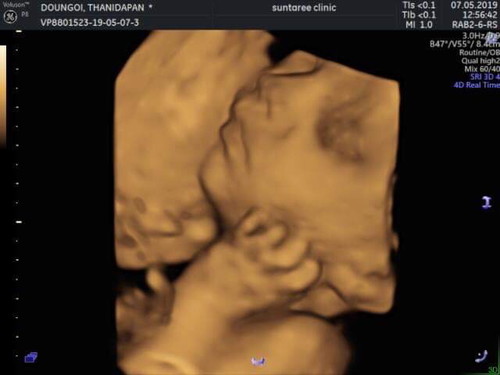

ซาวด์แบบ 4มิติ

หลงรักตั้งแต่อยู่ในท้องเลยเจ้าตัวน้อย??

แม่ซาวด์ตอนกี่วีคค่ะ บ้านนี้อยากซาวด์เหมือนกันตอนนี้ได้ 23 วีคค่ะ